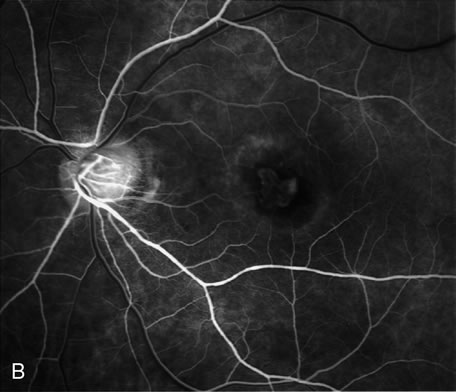

Fig. 20. A. Red-free photograph of a 20-year-old patient with sudden loss of vision to the level of 20/200. There is exudative, neurosensory macular detachment, a few hemorrhages, and lipid exudates. B. Fluorescein angiography reveals the presence of classic choroidal neovascularization (CNV), which appears to be juxtafoveal (<200 μ from fixation). Given the size of the CNV and its proximity to the fovea, it was decided to treat the patient with photodynamic treatment (PDT). C. Red-free photograph of the same eye 2 weeks after PDT; there is increased subretinal exudation D. Fluorescein angiography demonstrates that the CNV is still actively leaking. E. Red-free photograph 4 weeks after PDT demonstrates further increase in the size of the neurosensory macular detachment, subretinal hemorrhages, and lipid exudation. F. Fluorescin angiography reveals that the CNV has extended under the fovea. Given the young age of the patient, an inflammatory component of the neovascular process was suspected. It was decided to give a posterior, subtenon injection of triamcinolone acetonide, 40 mg/1 mL. G. Two weeks after steroid treatment there is partial reabsorption of the subretinal fluid. H. Fluorescein angiography demonstrates contraction of the CNV. I. Four weeks after injection of triamcinolone there is further reduction in the degree of neurosensory detachment; vision had improved to 20/60. J. Fluorescein angiography demonstrates that the CNV is smaller and less active (less leakage).